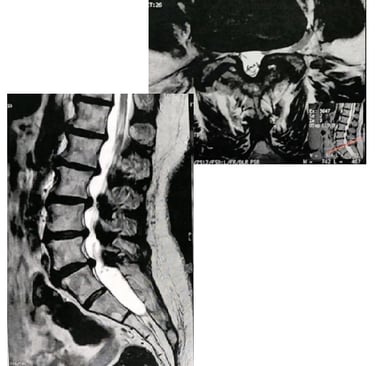

O diagnóstico começa com uma boa conversa (história clínica) e exame neurológico: avalio marcha, força muscular, reflexos, sensibilidade e testes provocativos. Em seguida, a ressonância magnética (RM) lombar é o exame de escolha, pois mostra tecidos moles, compressão nervosa e o grau de estreitamento.

Na RM axial T2, a classificação de Schizas (proposta por Schizas et al. em 2010) é uma ferramenta qualitativa simples e reprodutível para avaliar a morfologia do saco dural (onde ficam as raízes nervosas e o líquido cefalorraquidiano – LCR). Ela divide em 7 graus:

Grau A (estenose ausente ou mínima): LCR visível, raízes ocupam menos da metade do saco (subdividido em A1 a A4 conforme distribuição das raízes).

Grau B (moderada): Raízes ocupam todo o saco, ainda individualizáveis, mas com pouco LCR.

Grau C (grave): Nenhum LCR visível, raízes não reconhecíveis individualmente, mas gordura epidural posterior presente.

Grau D (extrema): Sem LCR nem gordura epidural posterior; saco dural aparece homogêneo e escuro.

Estudos de validação (como Ko et al., PLOS ONE 2020) mostram boa concordância inter e intraobservador, especialmente entre especialistas em coluna. Graus C e D indicam compressão mais severa e maior chance de necessidade cirúrgica.

Imagem ilustrativa da classificação de Schizas (adaptadas da publicação original):

Essas figuras mostram cortes axiais de RM e esquemas: note como o LCR (branco) diminui e as raízes (pontos escuros) se agrupam com o aumento do grau.